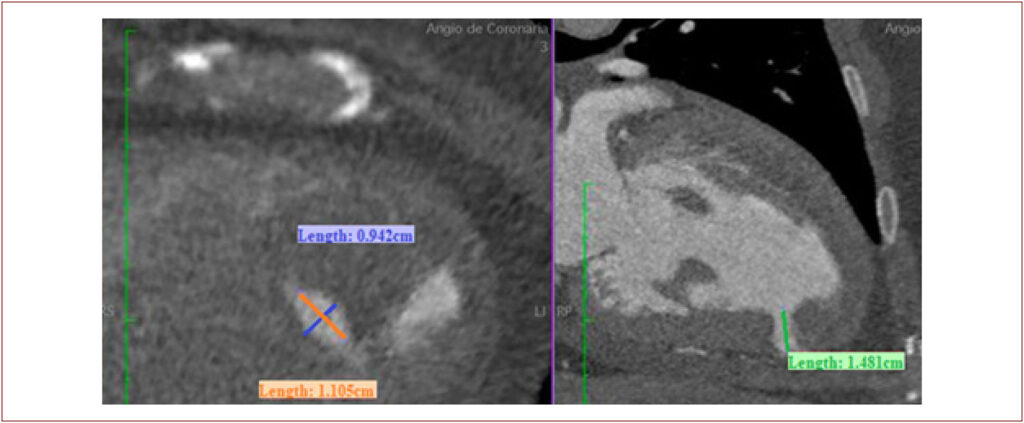

O pseudoaneurisma do ventrículo esquerdo (PAVE) é uma complicação rara após um infarto agudo do miocárdio (IAM), com risco significativo de ruptura se não tratado. Considerando a elevada morbimortalidade cirúrgica nesse contexto, tratamentos alternativos têm ganhado importância. Este caso descreve um fechamento percutâneo de um PAVE após IAM extenso com revascularização tardia.